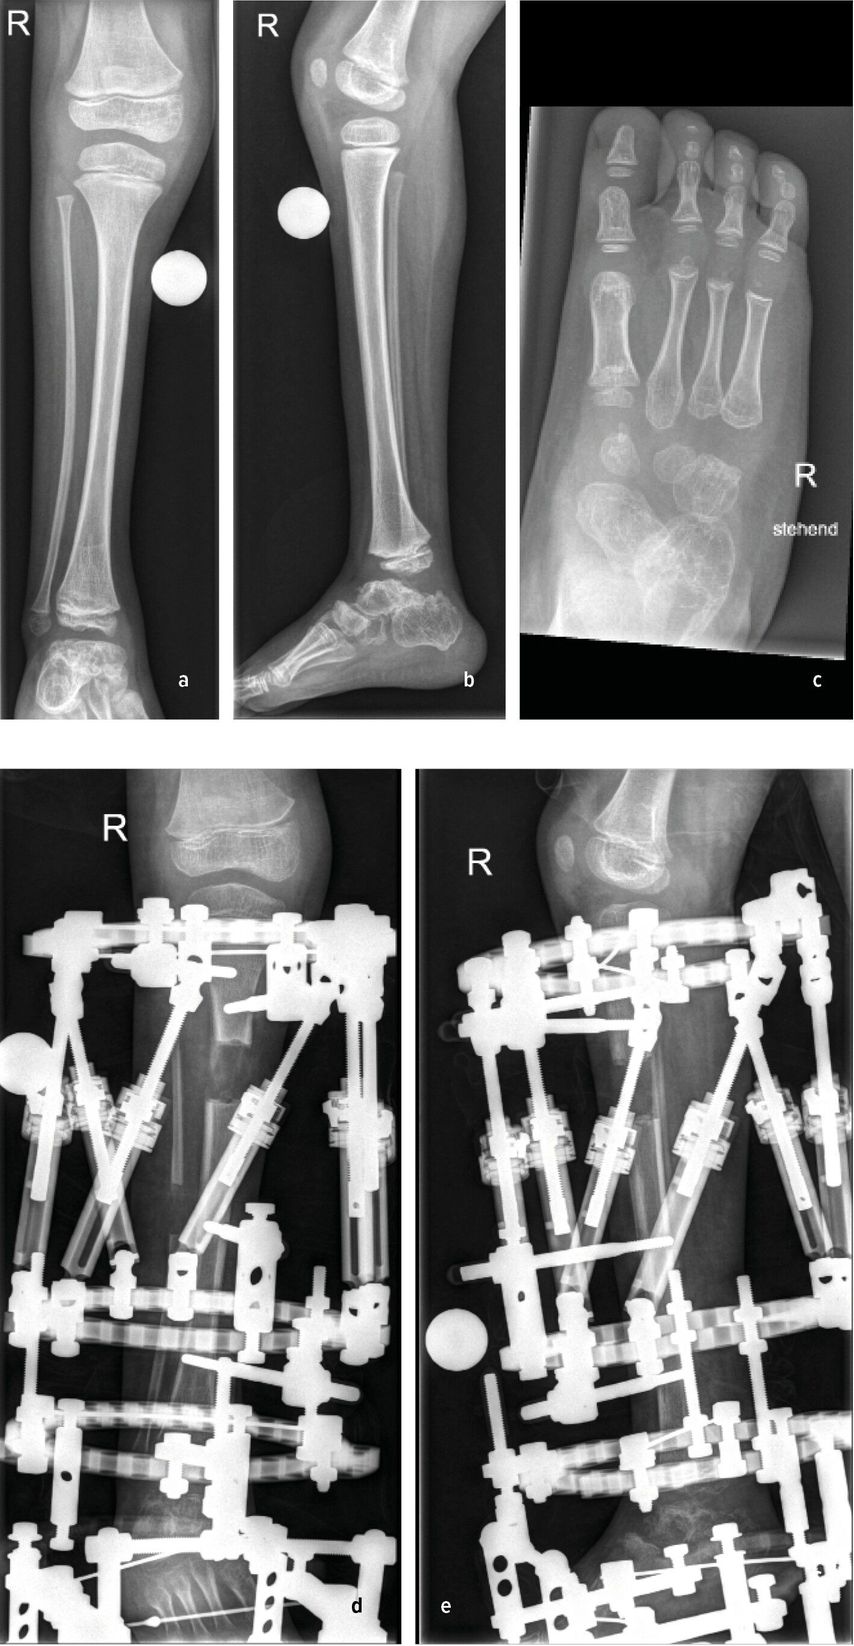

Die genaue Epidemiologie und Pathogenese des posteromedialen Bowings, auch bekannt als Crus valgum recurvatum, sind unbekannt. Einzelne dokumentierte Fälle in der Literatur lassen jedoch darauf schließen, dass es sich hierbei um eine sehr seltene Fehlstellung des Unterschenkels handelt, die vor allem die linke Extremität betrifft.15,16 Die Biegung der Tibia nach hinten und zur Körpermitte beträgt zwischen 25 und 70° und tritt typischerweise am Übergang vom mittleren zum distalen Drittel auf. In ausgeprägten Fällen kann die Fehlstellung bis zu 90° betragen. Der Fuß des Neugeborenen kann in schweren Fällen auf der Schienbeinkante zu liegen kommen. Bildlich repräsentiert dies der Fall eines 6 Wochen alten Mädchens mit posteromedialem Bowing der linken unteren Extremität mit typischer Biegung am Übergang vom mittleren zum distalen Drittel. Hier kommt der Fußrücken an der Unterschenkelkante zu liegen (Abb.3a,b). Differenzialdiagnostisch ist dabei an eine Calcaneo-valgus-Fehlstellung des Fußes zu denken.16 Eine spontane Rückbildung der Fehlstellung wird im Laufe des Wachstums bis zum 4.–5. Lebensjahr beobachtet.15 Konservative Maßnahmen beschränken sich initial auf sanfte Fußmassagen des Neugeborenen. In schweren Fällen kann eine graduelle Gipsredression eingesetzt werden.14

Abb. 3: 6 Wochen altes Mädchen mit posteromedialem Bowing der linken unteren Extremität (a+b) sowie postoperative Bildgebung

Verbleibende Fehlstellungen, insbesondere Rekurvation der Tibia, Beinlängendifferenz, Torsionsfehler oder Valgusfehlstellung der Tibia oder des Sprunggelenkes, bedürfen einer chirurgischen Intervention. Die dysplastische keilförmige Wachstumsfuge an der distalen Tibia begünstigt in einigen Fällen die Valgusfehlstellung im Sprunggelenk. Im Rahmen der Bildgebung präsentiert sich in dieser Abbildung ein 6 Jahre altes Mädchen mit einer selten auftretenden verbleibenden Valgusfehlstellung im Sprunggelenk bedingt durch eine dysplastische keilförmige Wachstumsfuge bei Z.n. Korrektur und Verlängerung mittels Fixateur externe und Stabilisierung mit intramedullärem Nagel (Abb.3c,d). Als chirurgische Therapien stehen hierfür die Wachstumslenkung an der distalen Tibia oder akute (supramalleoläre Korrekturosteotomien (Abb.3e,f) bzw. graduelle (externer Fixateur) Korrekturen zur Verfügung. Verbleibende Beinlängendifferenzen können durch eine Wachstumsbremsung der kontralateralen Seite bei geringer Beinlängendifferenz oder mittels gradueller Distraktionsosteogenese (externer Fixateur) therapiert werden.14,16,17